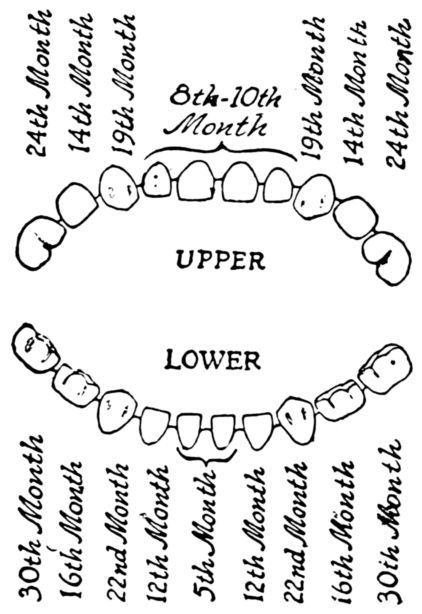

| 148. | Diagram of first teeth | 456 |